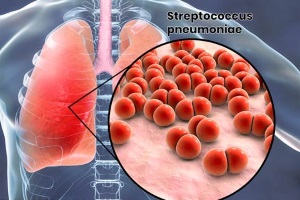

Пневмония – острое инфекционное заболевание, преимущественно бактериальной этиологии, характеризующееся очаговым поражением респираторных отделов лёгких с обязательным наличием внутриальвеолярной экссудации.

Внебольничная пневмония – довольно распространенная инфекционная патология. Заболеваемость ВП в Украине составляет около 0,5%, а летальность достигает 3%, причем в последние годы прослеживается четкая тенденция к прогрессивному повышению этих показателей.

Пневмония – распространенное заболевание органов дыхания, встречающееся у 3-15 человек на 1000 населения.

Внебольничная пневмония (ВП) является широко распространенной инфекцией, занимающей важное место в структуре заболеваемости и смертности населения во всем мире. Заболеваемость пневмонией в Европе составляет 2-15 случаев на 1000 человек в год [11]. В...

Пневмония относится к числу наиболее распространенных заболеваний человека и все еще остается серьезной медико-социальной проблемой. Так, заболеваемость пневмонией cреди взрослого населения в Украине в 1998–2000 годах составляла 4,3-4,7 на...